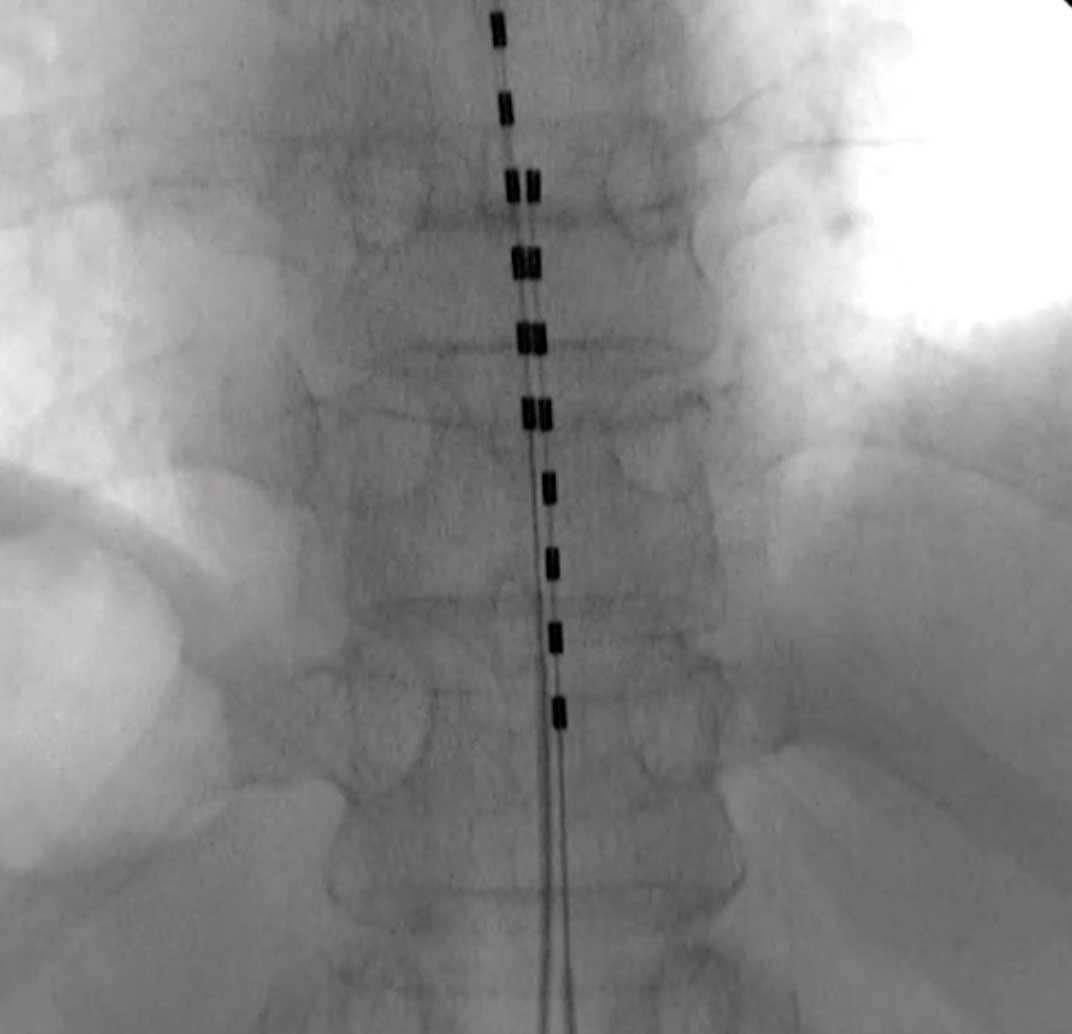

- 背中の真ん中に2-3cmの傷をつくり、脊髄刺激のための細いリードを1-2本、脊髄の外側にある硬膜外腔というところに留置します。

手術中の様子 - リードの端をジェネレーター(ペースメーカーのような刺激装置)につなげます。

手術後のレントゲン写真